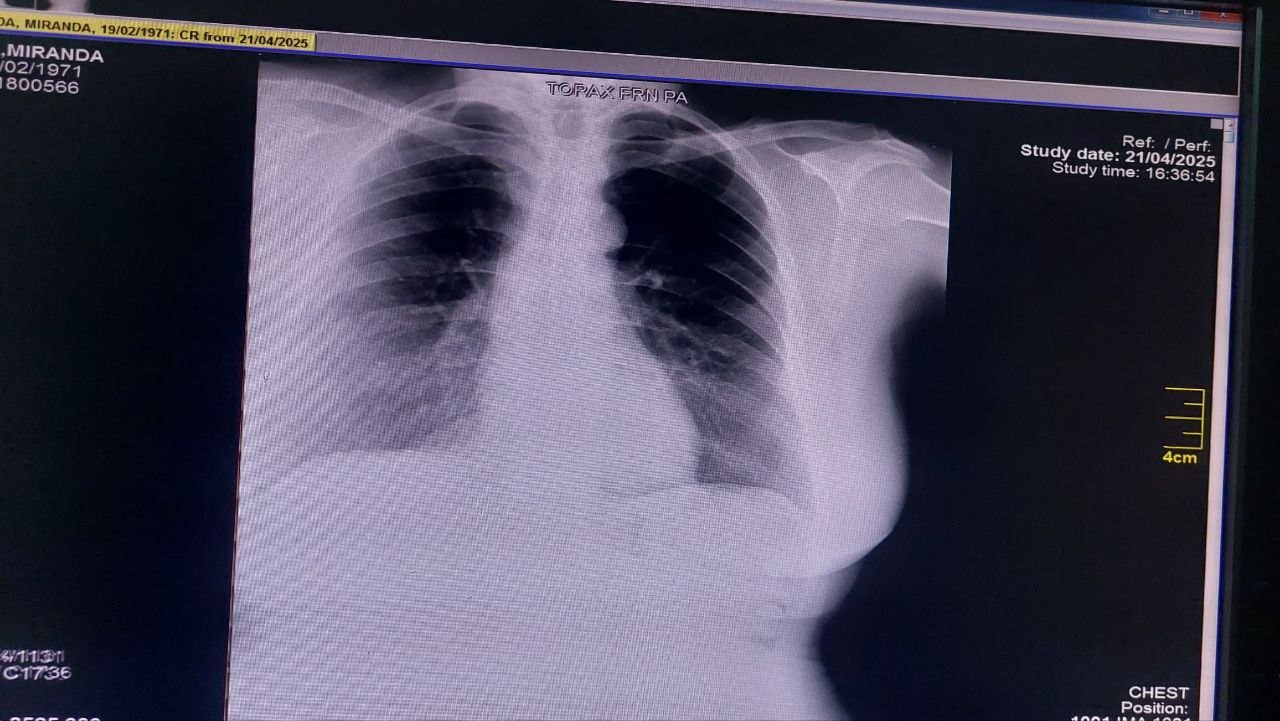

Ya el primer gran paso fue dado, su quimioterapia. En este segundo paso, Aida esta apta para ser intervenida quirúrgicamente, luego de haber recibido sus ciclos de quimioterapia, que han sido duros, pero no imposibles, estamos recaudando para poder realizar su MASTECTOMIA PARCIAL ONCOLOGICA, RECONSTRUCCION Y DISECCION AXILAR IZQUIERDA.

The first big step has already been taken: her chemotherapy. In this second step, Aida is ready for surgery. After receiving her chemotherapy cycles, which have been difficult but not impossible, we are raising funds to support her oncological partial mastectomies, reconstruction, and left axillary dissection.